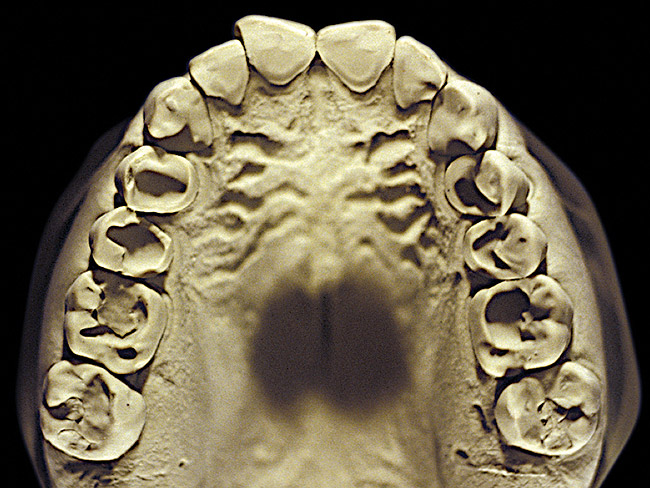

The patient shown in Figure 3 and Figure 4 exhibited severe NCLTS from bruxism. Examination of the casts indicated that the NCLTS was progressively greater toward the anterior teeth. Cupping and cratering was not present because there was no secondary cause. Figure 5 and Figure 6 detail another bruxism patient, but to a lesser degree and one with cupping/cratering caused by toothpaste. The cups or craters were not caused from bruxism because the teeth could not touch the bottom of the invaginations. In both featured patients, upon hand-articulating the casts, the NCLTS facets matched up and the diagnosis of bruxism was confirmed.

Figure 4  Advanced NCLTS from bruxism, maxillary arch.

Figure 4